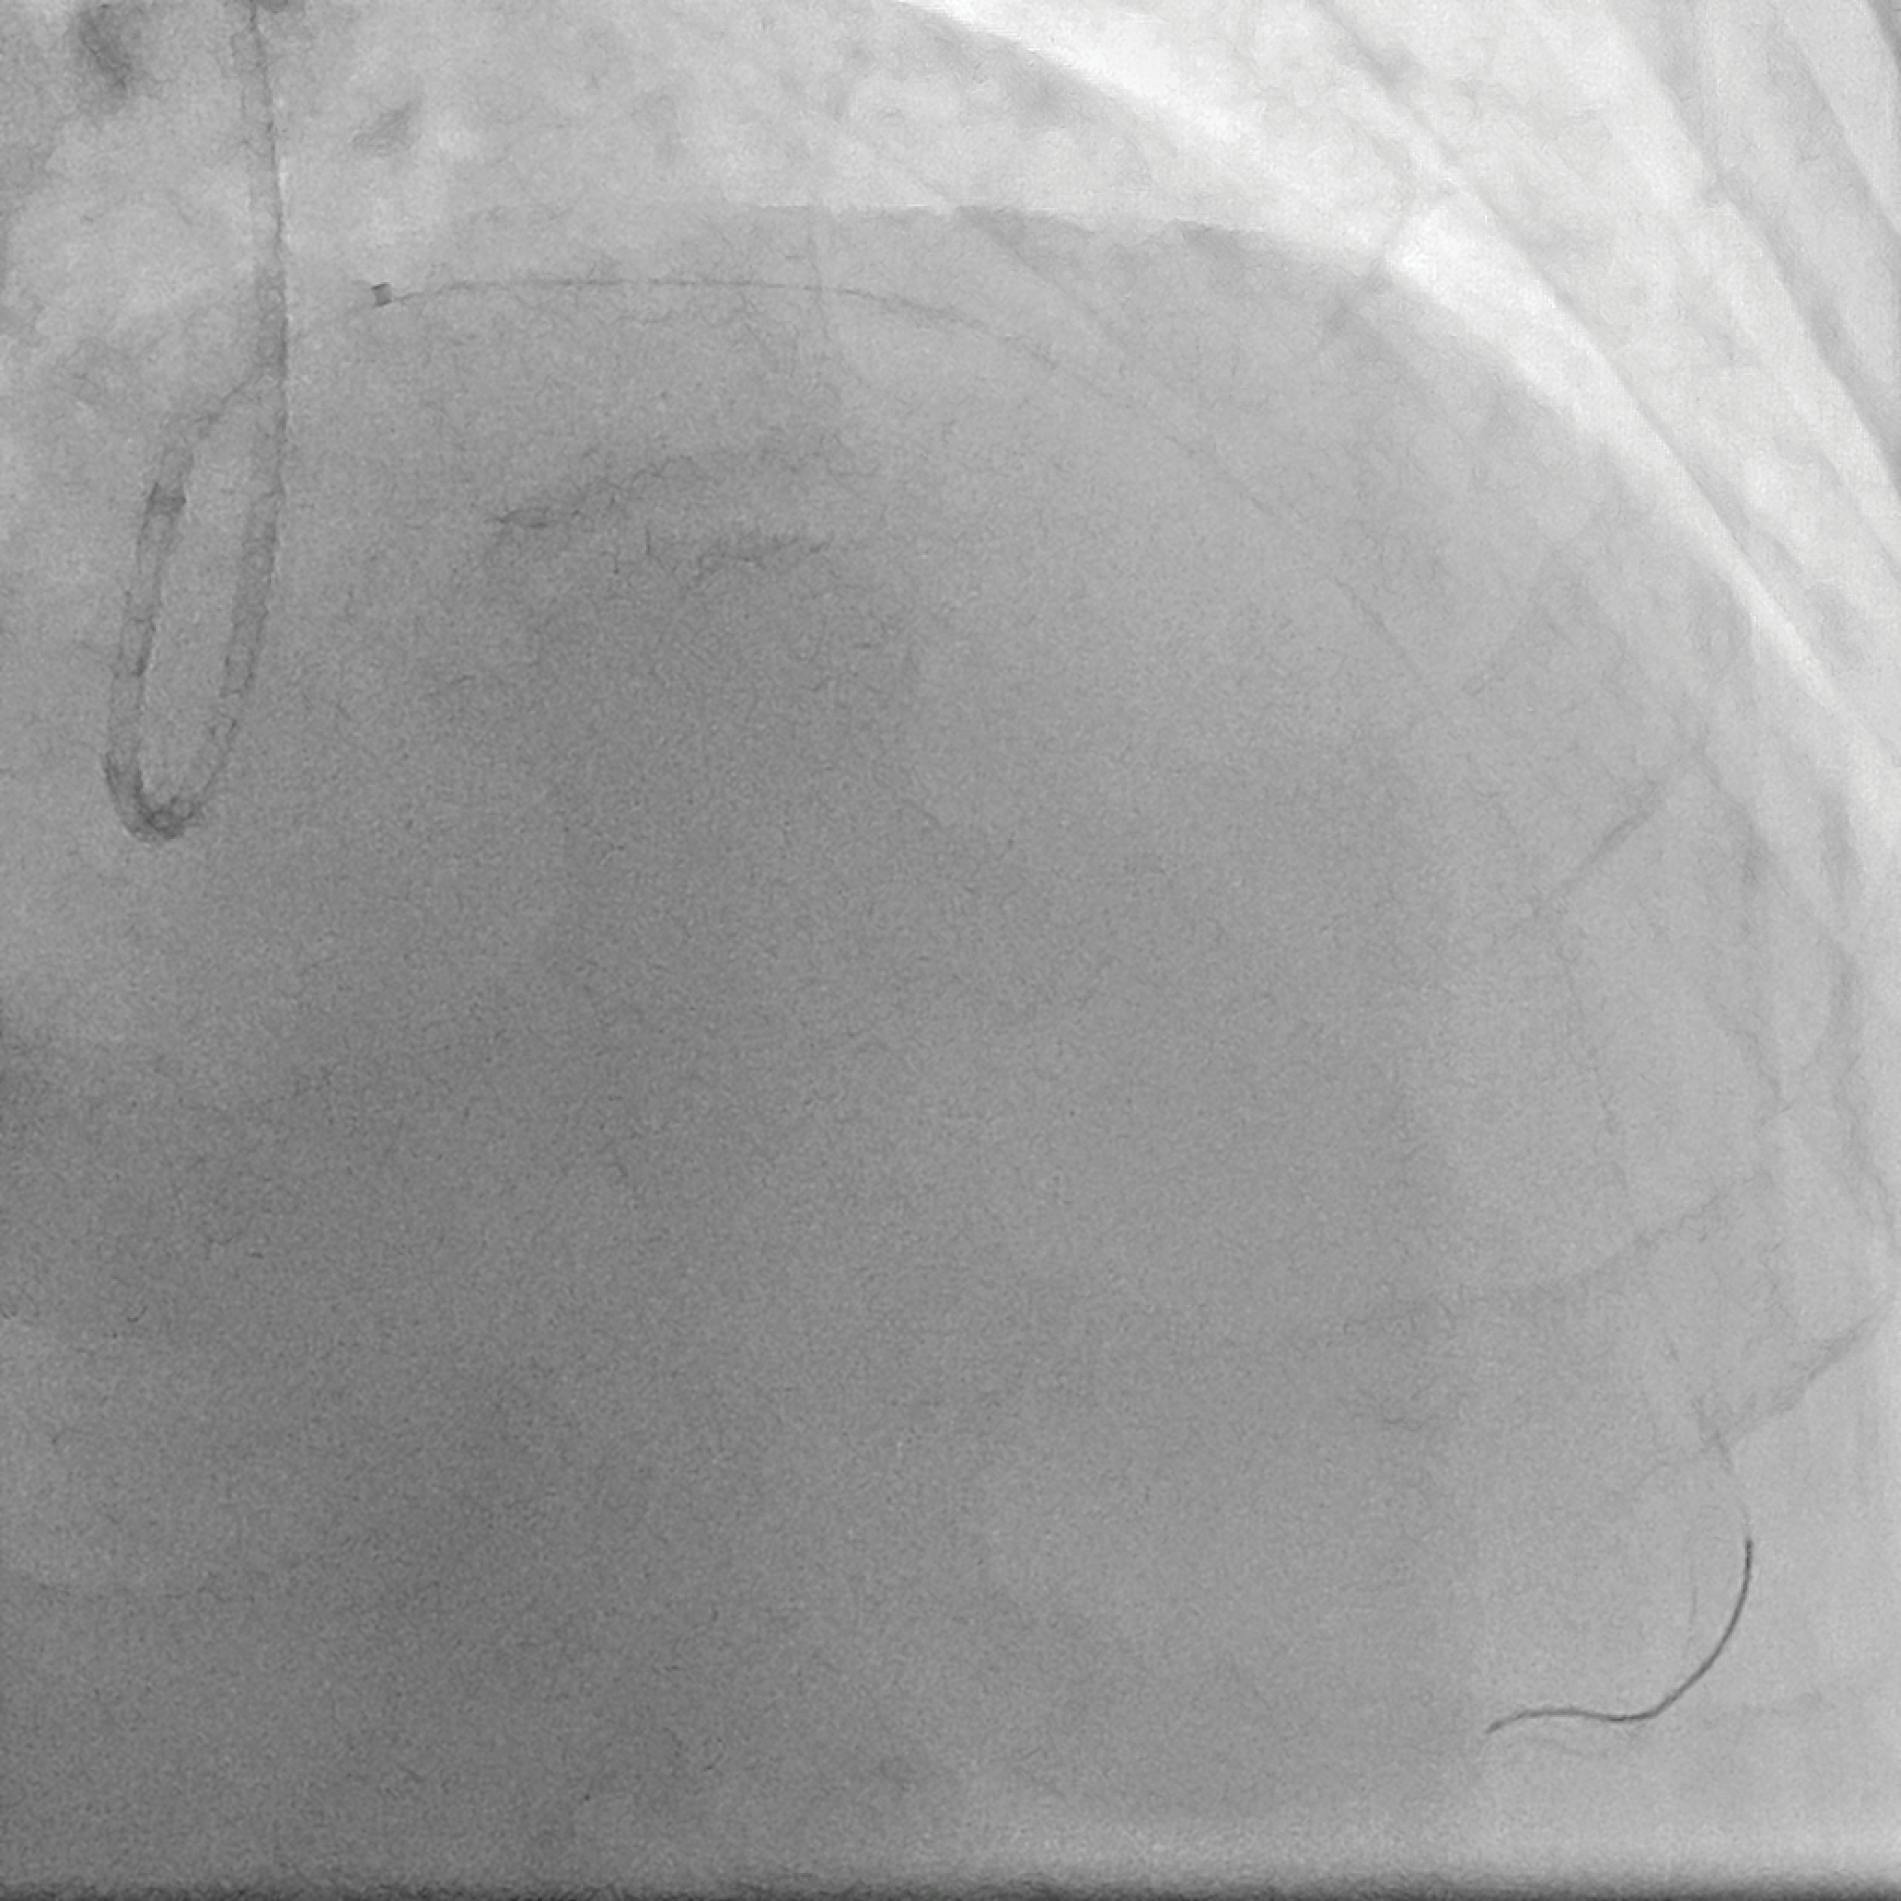

A 6-F guiding catheter (Adroit, Cordis) was positioned in the RCA over a 0.014-inch guidewire (Sion Black, Asahi Intecc Medical). After a gentle predilatation with a 2- X 15-mm balloon (Ryurei, Terumo Interventional Systems), thrombus aspiration with the CAT RX System was performed, and after two passes, the thrombus in the RCA was dramatically reduced and angiography showed a TIMI grade 3 flow (Figure 2). Optical coherence tomography (OCT) was performed to better visualize the aneurysm, the stenosis, and the amount of thrombus after the run with CAT RX. OCT confirmed reduction of the floating thrombus (Figure 3), and it was possible to appreciate red and organized thrombus in the canister filter at the end of the procedure.

Figure 2. Angiogram after aspiration.